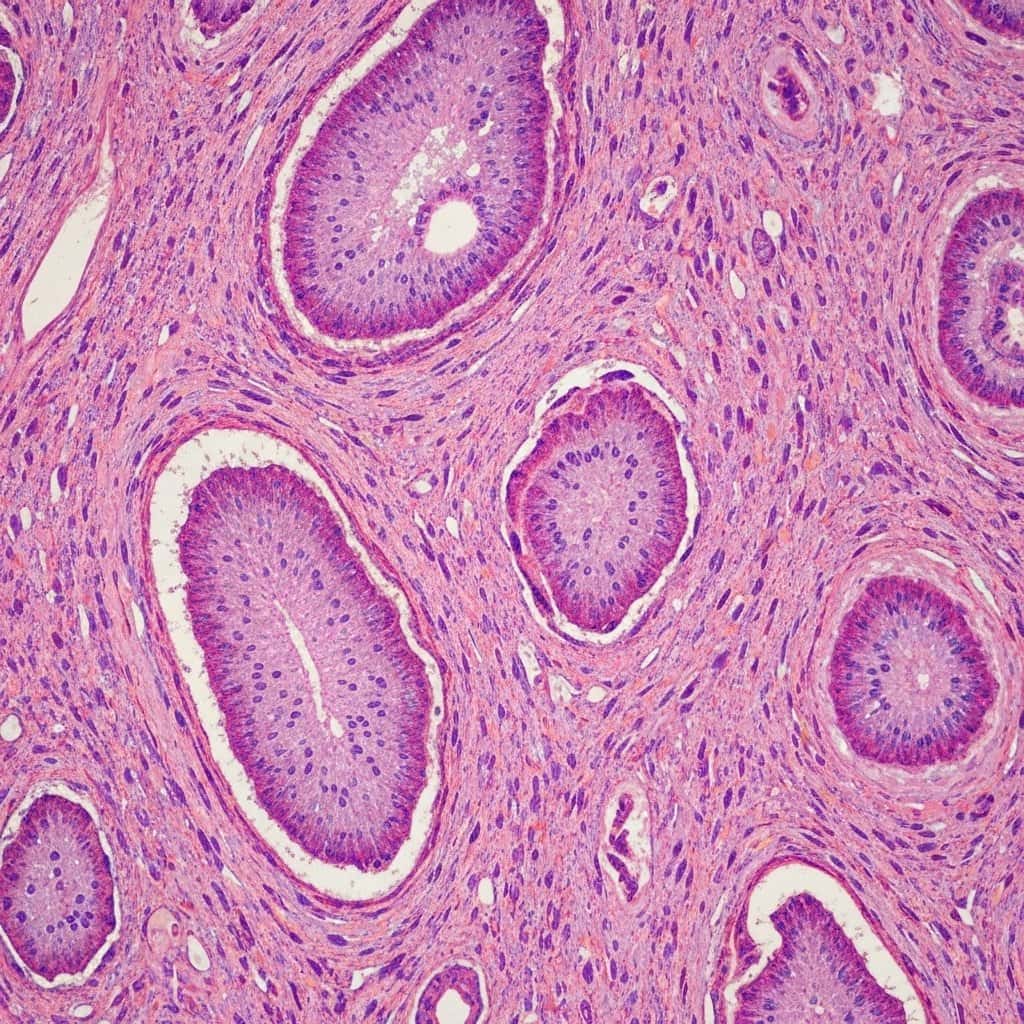

Tkanka epitelialna to wyspecjalizowany typ tkanki łącznej, która pokrywa powierzchnie ciała, wyścieła jamy ciała oraz tworzy gruczoły. Charakteryzuje się ona ściśle ułożonymi komórkami, które są silnie ze sobą połączone za pomocą specjalnych połączeń międzykomórkowych. Pomiędzy komórkami nabłonka znajduje się minimalna ilość substancji międzykomórkowej. Komórki te często ułożone są w jedną lub więcej warstw, a ich kształt może być bardzo zróżnicowany – od płaskich, przez sześcienne, po wysokie walcowate.

- Nabłonek sześcienny: Komórki mają kształt zbliżony do sześcianu, z jądrem umieszczonym centralnie. Odpowiada za wydzielanie i wchłanianie, można go znaleźć w kanalikach nerkowych czy przewodach gruczołowych.

- Nabłonek walcowaty: Komórki są wysokie i wąskie, przypominają walce. Często wyposażone są w mikrokosmki lub rzęski. Znajduje się w przewodzie pokarmowym (wchłanianie) oraz w drogach oddechowych (transport śluzu).